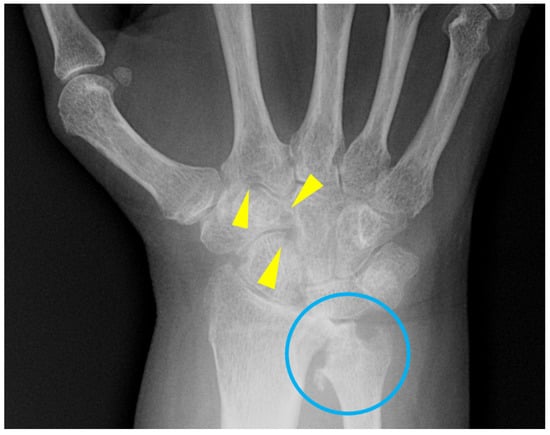

7. Calcium Pyrophosphate Dehydrate Arthropathy (CPPD)

Hallmarks | Sausage-digits Micky-mouse Pencil-in-cup. No osteophyte formation | Gull-wing (not specific, also can be seen in RA and PsA) | More prominent cysts Wrong distribution for primary OA Elbow and shoulders involved Chondrocalcinosis involving the triangular fibrocartilage complex (TFCC), scapholunate and lunotriquetral ligaments | Punched out erosions with overhanging edges | Reducible deformity and subluxations Non-erosive |